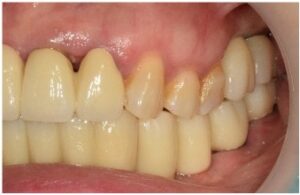

최종 보철물은

자연치아와 강도가 유사하고

심미적인 지르코니아 보철물로

마무리해 드렸습니다.

모든 치료가 마무리된

파노라마 사진과

구강 내 사진인데요.

환자분께서는

치료 후 양측 저작이 편안해지고

심미적으로 변한 모습에

만족해하셨습니다.